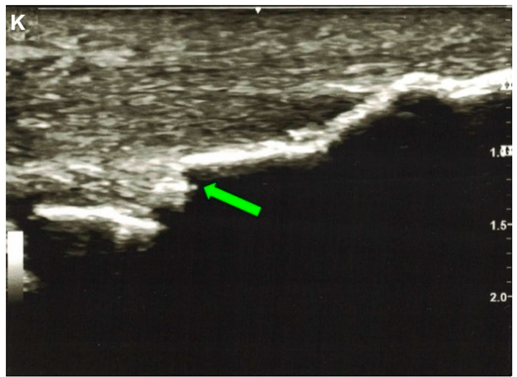

| Sullivan and Thurston, 2021 e [35] | A 72-year-old man. This image submission includes an ultrasound (Image K), lateral view x-ray (Image L), and an MRI (Image M) of a patient who presented to an orthopedic sports medicine clinic after feeling a “pop” while mowing his lawn. Image K is an ultrasound of the Achilles Tendon that depicts a segment of discontinuity (green arrow) within a linear hyperechoic signal. Image L and Image M show ossification of the Achilles Tendon and arrows (red and blue, respectively) indicate fracture of the ossified mass. The patient had no knowledge of the ossification, but he reported having lower leg surgery as a 2-year-old to correct for in-toeing. The patient was treated conservatively with casting and physical therapy. One year after the ossification and coexisting fracture of the ossified mass was discovered, he reported being fully functional without pain. | ![]() ![]() |